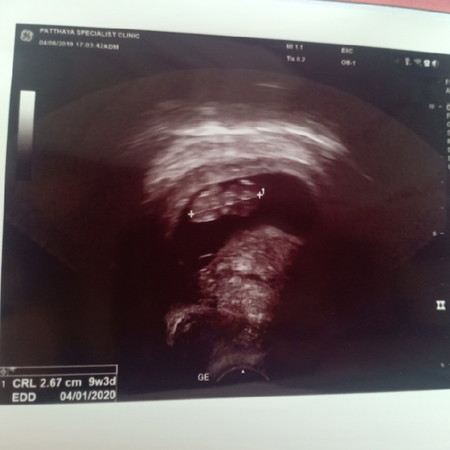

9 สัปดาห์ 4 วันคะ ซาวด์2รอบแล้วแต่ไม่เจอเลย ต้องตรวจผ่านช่องคลอดตลอด จะเป็นอะไรมั้ยคะ บางทีก็รู้สึกปวดท้องหน่วงๆด้วยคะ แม่ๆคนไหนเคยเป็นบ้างคะ จะตั้งครรภ์นอกมดลูกรึป่าวคะ ท้องแรกคะ แอบกลัว ?

ถ้าปวดท้องหน่วง ๆเป็นอาการปกติค่ะเพราะมดลูกขยาย ยังไงขอให้เจอน้องนะคะ